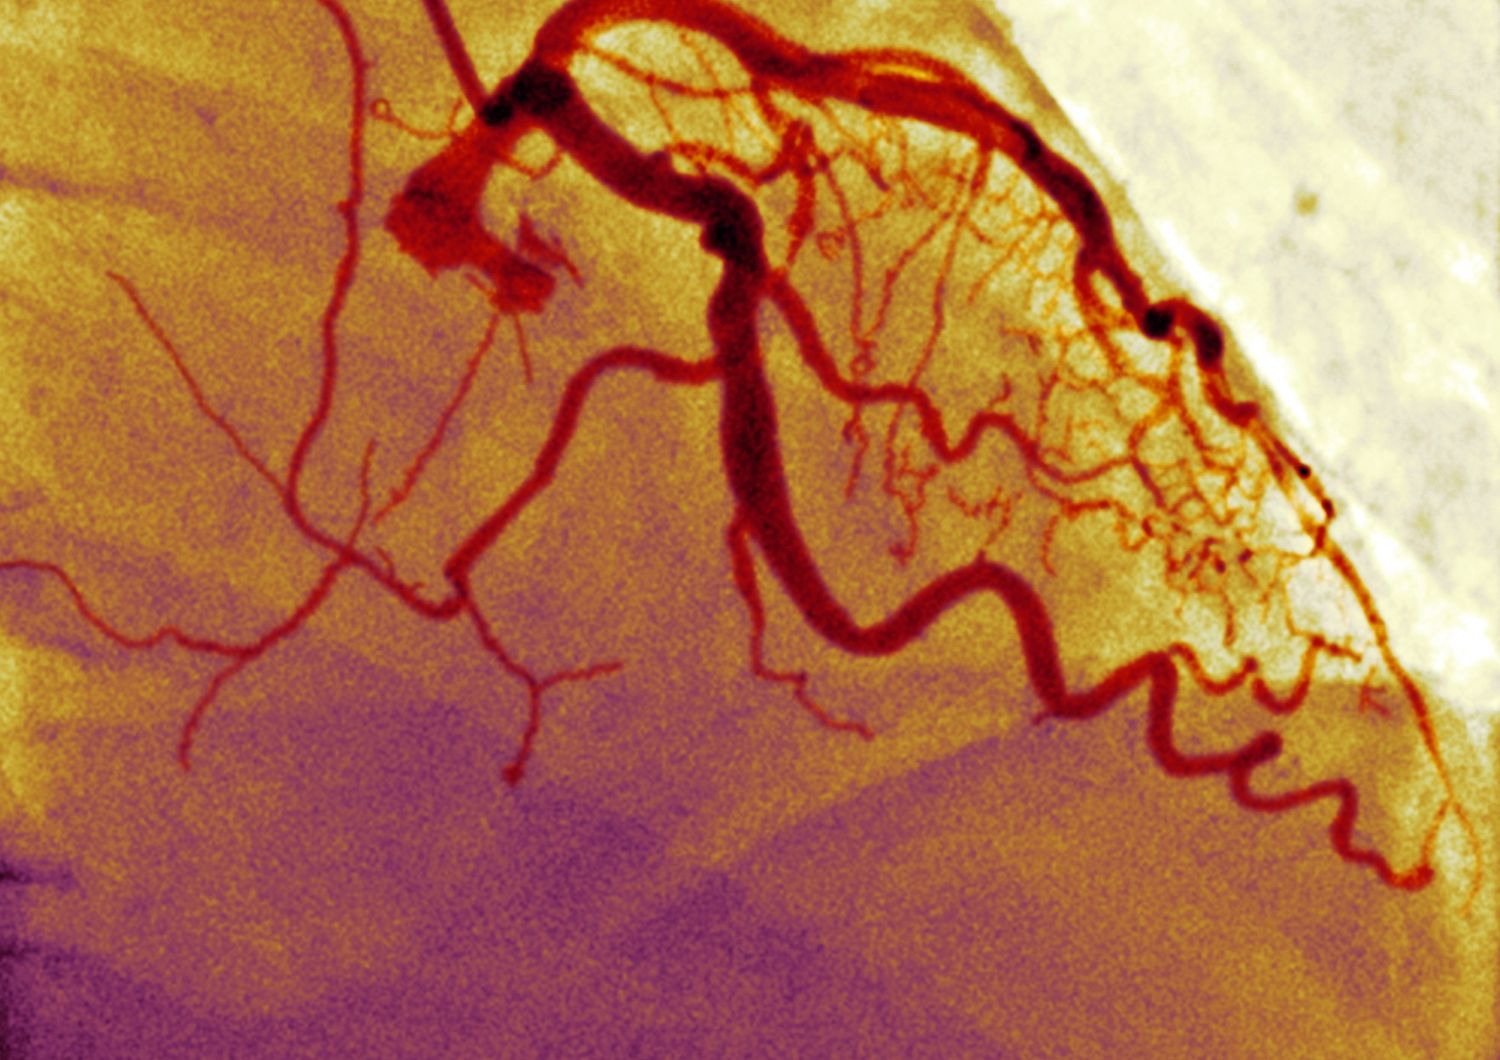

Washington - Creati vasi sanguigni bioingegnerizzati per i pazienti affetti da malattia renale in dialisi. A farlo e' stato uno scienziato di Yale insieme a ricercatori della Duke University, chirurghi provenienti dalla Polonia e dagli Stati Uniti. I risultati sono stati pubblicati sulla rivista The Lancet. Le persone con insufficienza renale hanno bisogno della dialisi, che viene spesso somministrata attraverso un innesto sintetico trapiantato nel braccio. Tuttavia, questi innesti aumentano il rischio infezione e di altre complicazioni. Per questo i ricercatori hanno creato vasi artificiali che sembrano essere piu' sicuri e resistenti rispetto alle altre versioni sintetiche comunemente utilizzate.

I nuovi vasi bioingegnerizzati sono stati testati su 60 pazienti in 6 centri di ricerca. Per crearli, i ricercatori hanno prima isolato le cellule vascolari provenienti da donatori umani e cresciuti in coltura. Gli studiosi hanno poi utilizzato un'impalcatura biodegradabile a forma di vaso sanguigno. Il tessuto ottenuto e' stato poi immerso in nutrienti ed ha acquisito le proprieta' fisiche dei vasi sanguigni reali. Dopo 8 settimane, l'impalcatura si e' degradata e sono state lavati via i componenti cellulari con una soluzione speciale. La struttura proteica rimanente "non ha cosi' nessuno dei componenti cellulari che possono causare il rigetto dei tessuti. Un anno dopo l'impianto, i vasi bioingegnerizzati sembravano sicuri e funzionali. .